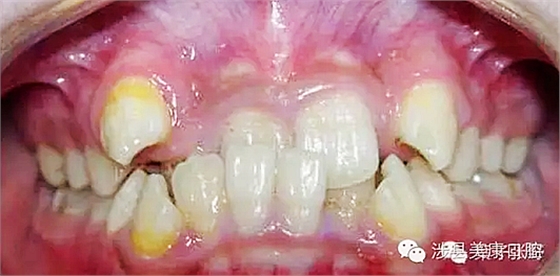

影響乳牙下方的恒牙胚。

造成恒牙釉質(zhì)發(fā)育不良。

![%ZE{HJY7[$E@]P[}W0CMW~4.png %ZE{HJY7[$E@]P[}W0CMW~4.png](/Mobile/UploadFiles/FCK/2017-04/6362664370621357178946990.png_280.jpg)

引起恒牙萌出亂位。

引起牙齦發(fā)炎。

引起牙齒錯(cuò)位。